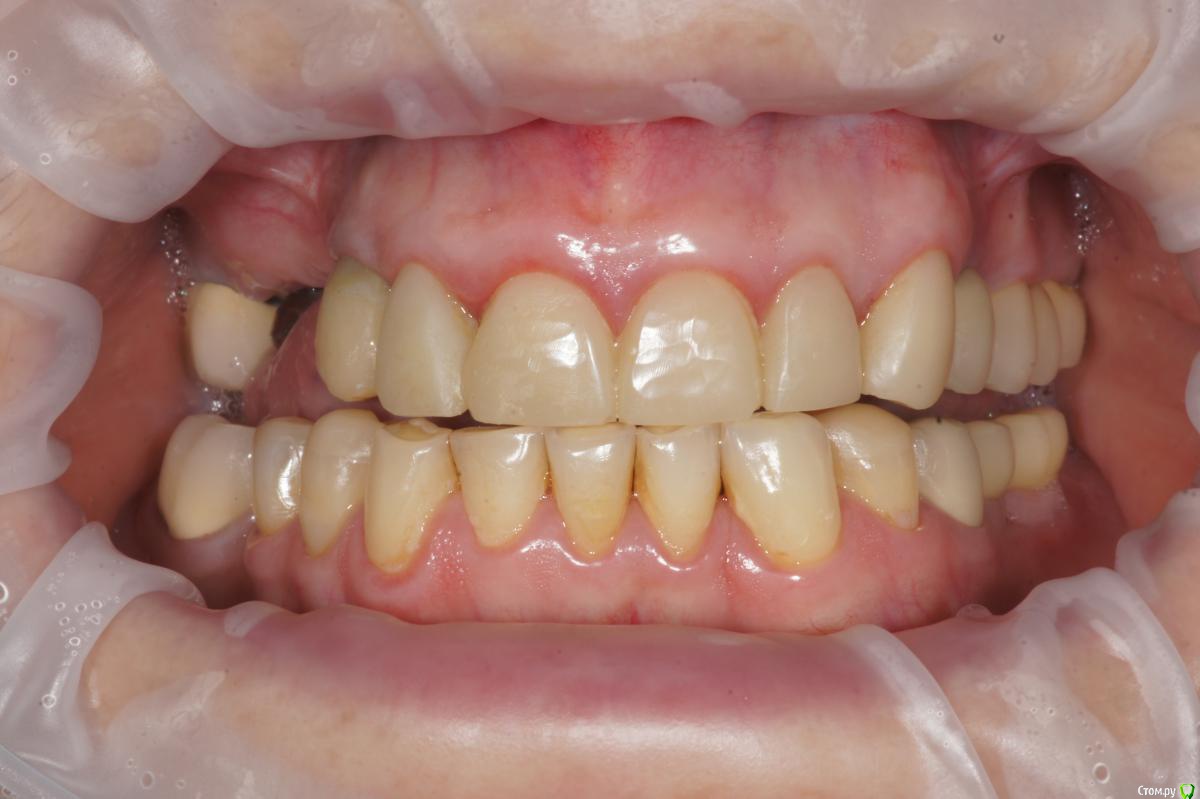

Alexandr_doc Опубликовано 21 сентября, 2018 Поделиться Опубликовано 21 сентября, 2018 Доброго всем времени! Пациентку протезировал доктор, которого уволили по ряду причин, обратилась ко мне на этапе после протезирования с жалобами на болезненность в области фронтальной группы зубов 1.2, 1.1, 2.1, 2.2, 2.3 при дотрагивании языком или пальцем. Перкуссия положительная как в вертикальном так и горизонтальном направлении. Установлены одиночные керамические коронки на каркасе из диоксида циркона. Отек, покраснение в области переходной складки отсутствует, также отсутствует болезненность при пальпации. Подвижность 1 степени. Прилагаю фотографии на этапе обращения. Ранее, на этапе протезирования было принято решение о депульпировании фронтальной группы тк присутствовала пульпитная симптоматика, после чего состояние улучшилось и остается стабильным по сей день. Предположил несколько причин оставшейся симптоматики: 1) несостоятельно проведенное эндо лечение - вариант отмел тк по прицельным снимкам и кт отсутсвуют очаги воспалительных процессов 2) некорректно изготовленные искуственные коронки ( глубокая поддесневая препаровка и агрессивный контур коронки ) 3) - окклюзионная перегрузка. Совместно с пацинеткой принято решение о снятии коронок во фронтальном отделе, была предупреждена о том, что возможно не получить хорошей динамики. С переменным успехом картина после нескольких корректировок временных коронок остается преждней. Болезненность на прежднем уровне, плюс по ходу наблюдения пришлось снять мост с опорой на уровне имплантатов, тк имели место быть воспалительные процессы в проекции имплантата 1.5. С удовольствием отвечу на все вопросы и приму любую критику. Ссылка на комментарий

Corsag21 Опубликовано 21 сентября, 2018 Поделиться Опубликовано 21 сентября, 2018 (изменено) Точно ли на кт нет изменений на корнях зубов? Мне на рентгеновских снимках что-то видится. жесткая каппа на верхний зубной ряд - я бы начал с этого.Нижние резцы устойчивы?Чем вам не нравится глубокая поддесневая препаровка? Десна выглядит также как и на интактных зубах НЧ.Как проверяется работа на предмет локальной перегрузки - не знаю, расскажите пожалуйста. Изменено 21 сентября, 2018 пользователем Corsag21 Ссылка на комментарий

Alexandr_doc Опубликовано 21 сентября, 2018 Автор Поделиться Опубликовано 21 сентября, 2018 Точно ли на кт нет изменений на корнях зубов? Мне на рентгеновских снимках что-то видится. жесткая каппа на верхний зубной ряд - я бы начал с этого.Нижние резцы устойчивы?Чем вам не нравится глубокая поддесневая препаровка? Десна выглядит также как и на интактных зубах НЧ.Как проверяется работа на предмет локальной перегрузки - не знаю, расскажите пожалуйста.На кт изменений нет, мне хотелось их найти, но нет. Мне будет не сложно сделать срезы и приложить их к посту, рассматривал некачественное эндо как один из первых причинных факторов. Жесткая капа какая? Какой дизайн и схему порекомендуете? Десна действительно сейчас выглядит также как и в других участках. При гипсовке в ЦС проверены: наличие первого контакта на фронтальной группе, проверена схема направляющих, распределение контактов на моделях. Ссылка на комментарий